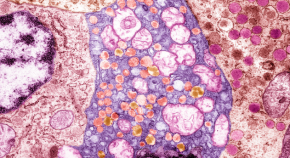

First-in-human studies provide hope that islet replacement therapies derived from stem cells will prove safe and effective in people with type 1 diabetes, but hurdles remain.